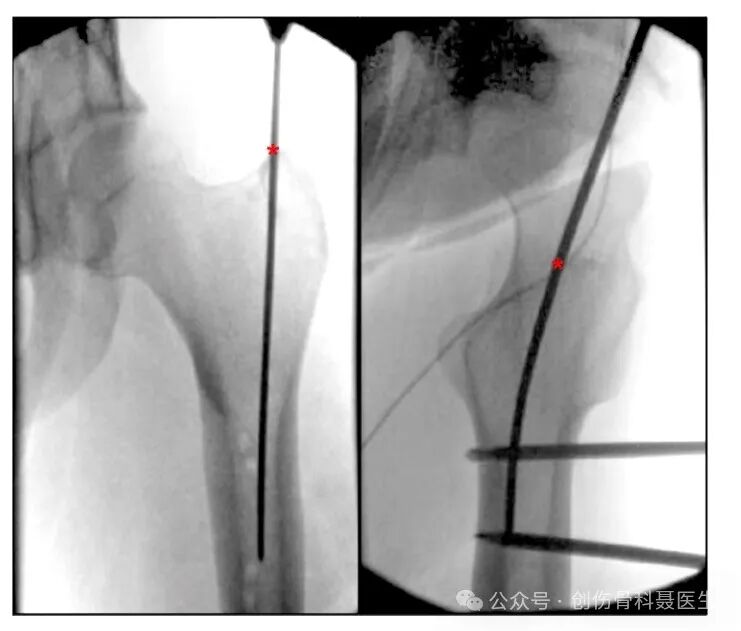

切口入点:❶大转子进针点:从大转子尖顶点的进针点,在正位中朝向髓腔的内侧,侧位中为大转子中心与股骨髓腔中心连线,大转子顶点进针点常用于肥胖患者,这种手术技术要求较低,与梨状窝进针点相比,它可以提供更少的手术时间和更低的并发症风险;

❷梨状窝进针点:大转子内侧的凹陷(股骨颈底部凹陷处)的闭孔外肌附着区